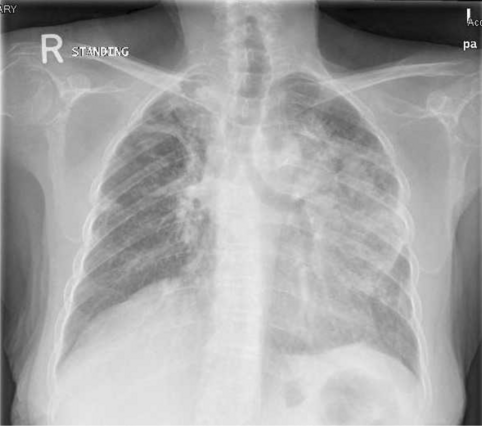

a Fused FDG PET-CT image with lung window showing intense uptake bilaterally more prominent in the left apical mass. b maximum intensity projection representation of whole body FDG distribution showing metastatic pulmonary adenocarcinoma (stage IV)—note FDG avidity is more on left side

Later on, the patient was started on immunotherapy pembrolizumab monotherapy, 200 mg every 3 weeks, as first-line treatment. PET CT following six cycles of pembrolizumab showed mixed response with overall moderate progression (Fig. 4a, b).

a, b PET CT (lung window) following six cycles of pembrolizumab showed mixed response with overall moderate progression

The time to diagnosis of TB in the current case occurred after six cycles of Pembrolizumab. TB was confirmed microbiologically by PCR and AFB. The patient received her BCG vaccine as part of the local child immunization program. Our case gave a history of sick contact with a patient with active TB infection 10 years ago, but there was no documentation of latent TB or previous TB infection prior to initiation of ICPs. The mixed response noted on 14th July 2019 PET CT (Fig. 4) was not perceived as pseudoprogression-like phenomenon as overt disease progression was confirmed by 26th August 2019 CT chest and abdomen as illustrated (Fig. 8).